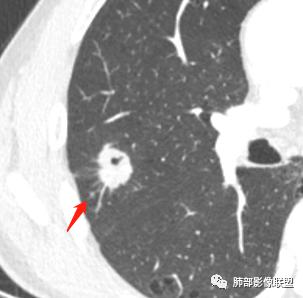

影像学改变:

1.右肺上叶后段类圆形结节影,密度不均,有坏死空洞,坏死比较彻底,内外壁都较清楚。

2.病灶有浅切迹,没有深分叶,毛刺大多细长且柔软。

3.可见棘状突起及胸膜牵拉,但未见胸膜凹陷。

什么意思?结节影有牵拉的动作,但似乎“出工不出力”,收缩力羸弱!

4.病灶轻到中度强化。病灶内血管走行较完好,病灶旁血管局部显示粗大。

5.支气管关系不确定。

6.灶周见小结节影(卫星灶),边界不甚清晰。